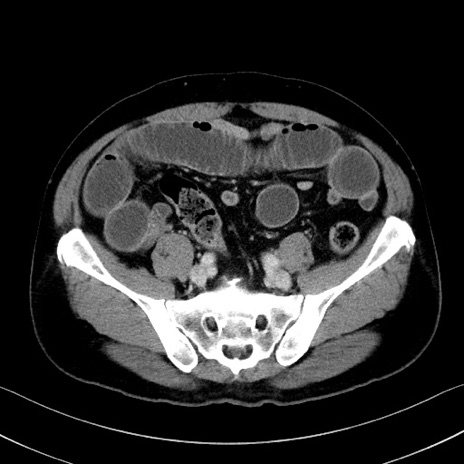

冠状断像

【症例】70歳代 男性

【主訴】腹部膨満、嘔吐

【現病歴】昨日より腹部膨満感出現。本日増悪し、仙痛出現。嘔吐あり、受診。

【既往歴】糖尿病、胆摘後

【身体所見】BP 149/80mmHg、HR 74/min、BT 35.9℃、腹部:膨満、軟、圧痛なし。腸雑音減弱あり。上腹部正中切開瘢痕あり。

【データ】WBC 13500、CRP 1.72